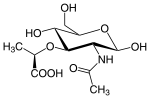

N-Acetyl- β-D-Glucosamine- This sugar is essential for optimal health and function in the body. It aids in cell communication. It also plays a role in how the immune system reacts with HIV and tumors. This also plays a role in osteoarthritis and helps in cartilage formation. It has been shown to play a role in nerve functioning for learning in mammals. This molecule has multiple uses such as limiting cholesterol absorption and decreases insulin secretion. Some receptors have been found in the thyroid to transport iodine proteins. It is found in multiple glands of the body and plays some role in the organ’s function. Muramic Acid-This sugar is a main component of bacteria cell walls and it is a derivative of peptidoglycan. It is used in gas chromatography for laboratory experiments.

N-Acetylmuramic Acid- This is also found in peptidoglycans of bacterial cell walls. It is a the product after N-acetylglucosamine that has been condensed with lactic acid. In bacteria, phosphophoenolpyruvate adds the lactyl group to C3 of N-acetylglucosamine. Beta-lactams compete for binding with transpeptidases, enzymes that catalyze the formation bonds between N-acetylmuramic acid-based peptide chains. Chlamydia lacks N-acetylmuramic acid in its cell walls which is the reason why penicillin does not treat the disease.

'N-Acetyl-d-glucosamine' is the main component of the polysaccharide in chitin, the substance that makes up the tough outer skeleton of arthropods and insects.